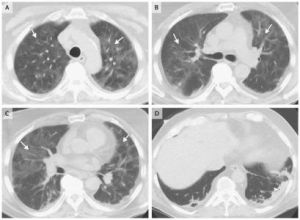

肺功能的異常和嚴重程度與疾病的階段有關,典型者為中、重度的限制性通氣功能障礙、DLCO的下降。肺泡-動脈氧的梯度的升高,如果伴有哮喘則有阻塞性的改變。X線表現與胸膜相對的周圍漸進的密度增強的浸潤影,邊緣不清,呈非節段性、亞段和葉的分布,多位於肺外周2/3,而肺門處較透明,故稱為"肺水腫反轉形狀",陰影易在原處復發。潑尼松治療後陰影很快吸收。與Loffler'綜合徵相反,CEP的肺浸潤為非遷移性,很少有胸腔積液。不典型的X線表現包括結節狀浸潤、瀰漫性毛玻璃樣的肺泡填充征。胸部CT檢查對於臨床懷疑而X線表現不典型的病例可作CT檢查,CT的表現,在症狀發作的前幾周,大部分表現為典型的密度區、周圍局部的肺泡實變,當症狀持續2個月以上,可見有條索帶狀不透光區,並見縱隔淋巴結腫大。